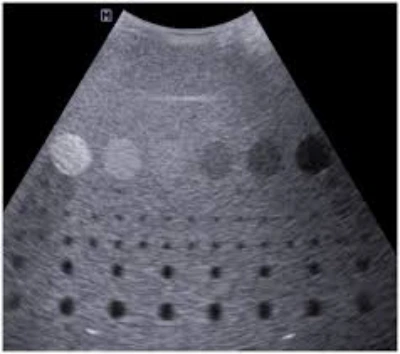

O reparo de sondas ultrassom envolve inspeção, calibração e ajustes de componentes que promovem funcionamento correto e imagens precisas.

Técnicos especializados realizam manutenção preventiva e corretiva, assegurando confiabilidade no diagnóstico e continuidade nos atendimentos clínicos.

O reparo de sondas ultrassom é essencial para assegurar o bom funcionamento dos equipamentos e a precisão dos exames realizados.

Com a inspeção regular e os ajustes necessários, é possível evitar falhas técnicas que comprometam a qualidade das imagens e a segurança dos pacientes.